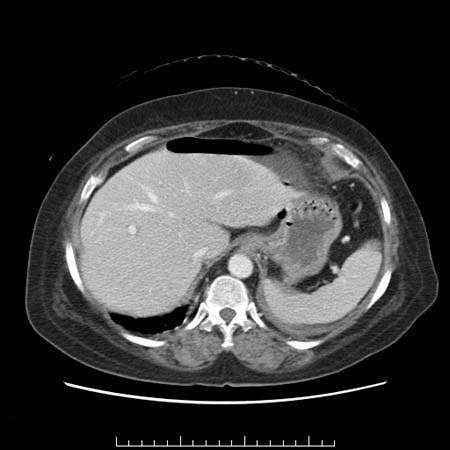

57歳 女性

解説:胃潰瘍穿孔

前腹壁下に異常ガス(腹腔内遊離ガス)があり、腹水と相まって液面形成(

図1

、

図2

)している。遊離ガスが上腹部に多く分布しているので、まず胃と十二指腸を確認する。胃前庭部には深掘れ潰瘍を疑う液面形成(

図3

)があり、胃壁の肥厚(

図4

)も見られることから胃潰瘍の遊離穿孔と考えた。前庭部周囲(

図5

)や胃結腸間膜部(

図6

)には炎症波及による脂肪織不整がある。

骨盤部の腹水(

図7

)。

十二指腸球部や胆嚢周囲にも脂肪織不整があるが主病変は胃前庭部である。S状結腸は虚脱しているのみで異常は指摘できない。

腹部身体所見と全身状態から保存的治療を選択した(冠状断再構成CT像:

図8

穿孔性胃潰瘍。

内科的治療を継続したが最終的には胃亜全摘術を行い良性潰瘍であった(

図9